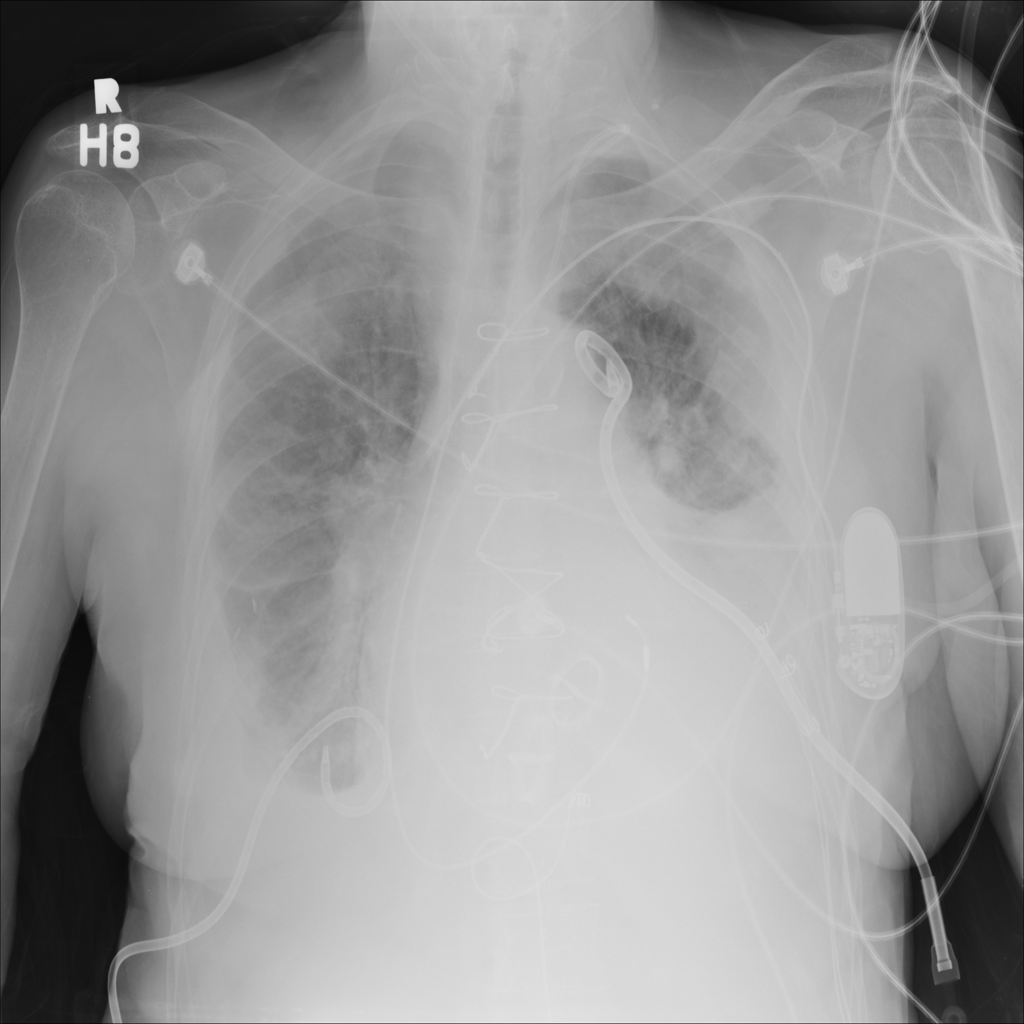

PAT-3384 · IMG-021Cardiomegaly

PAT-3384 · IMG-021

AP